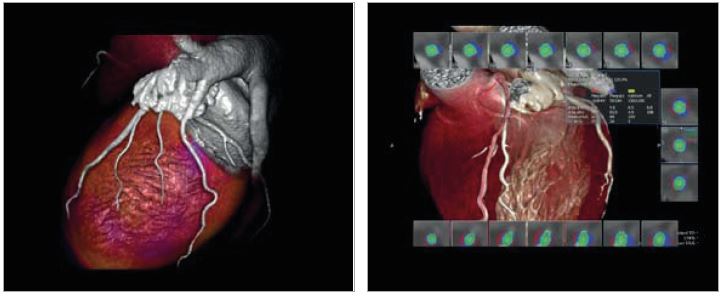

• Значне скорочення часу MPT-обстеження завдяки автоматичному визначенню необхідних площин серця, використовуючи опцію CardioLine+

• Покращену діагностику, лікування та планування за допомогою гібридної візуалізації. Використовуючи технологію Smart Fusion, можна співвіднести ступінь коронарного стенозу на комп'ютерній томографіїз інформацією про розтягнення міокарда, отриманою за допомогою ультразвуку на навколишній міокардіальній території.

• Інтегрувати та аналізувати клінічні дані з багатьох модальностей за допомогою програми Vitrea Advanced Visualization.

Vitrea — це мультимодальне рішення. Наш набір передових програм надає повноцінні рішення для розширеної20,3D і 4D візуалізації, які використовуються для обробки та аналізу клінічних даних з різних модальностей - MPT, КТ, CR, DX, RG, RF, УЗД, ХА, NM, ПЕТ,ПЕТ/КТта ОФЕКТ.

Global Illumination